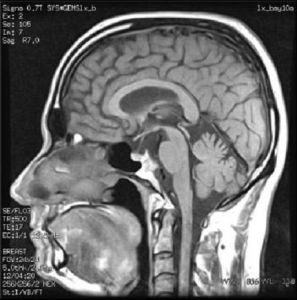

3.磁共振成像(MRI)

對垂體軟組織的分辨力優於CT,可彌補CT的不足

MRI檢查,是診斷垂體瘤最重要的工具,可以清楚地顯示腫瘤的大小,形態,位置,與周圍結構的關係。即使直徑2~3毫米的腫瘤也可以顯示出。但還有部分腫瘤的信號與周圍正常垂體組織近似,兩者難以區分,還需要結合臨床表現和內分泌檢查進行診斷。